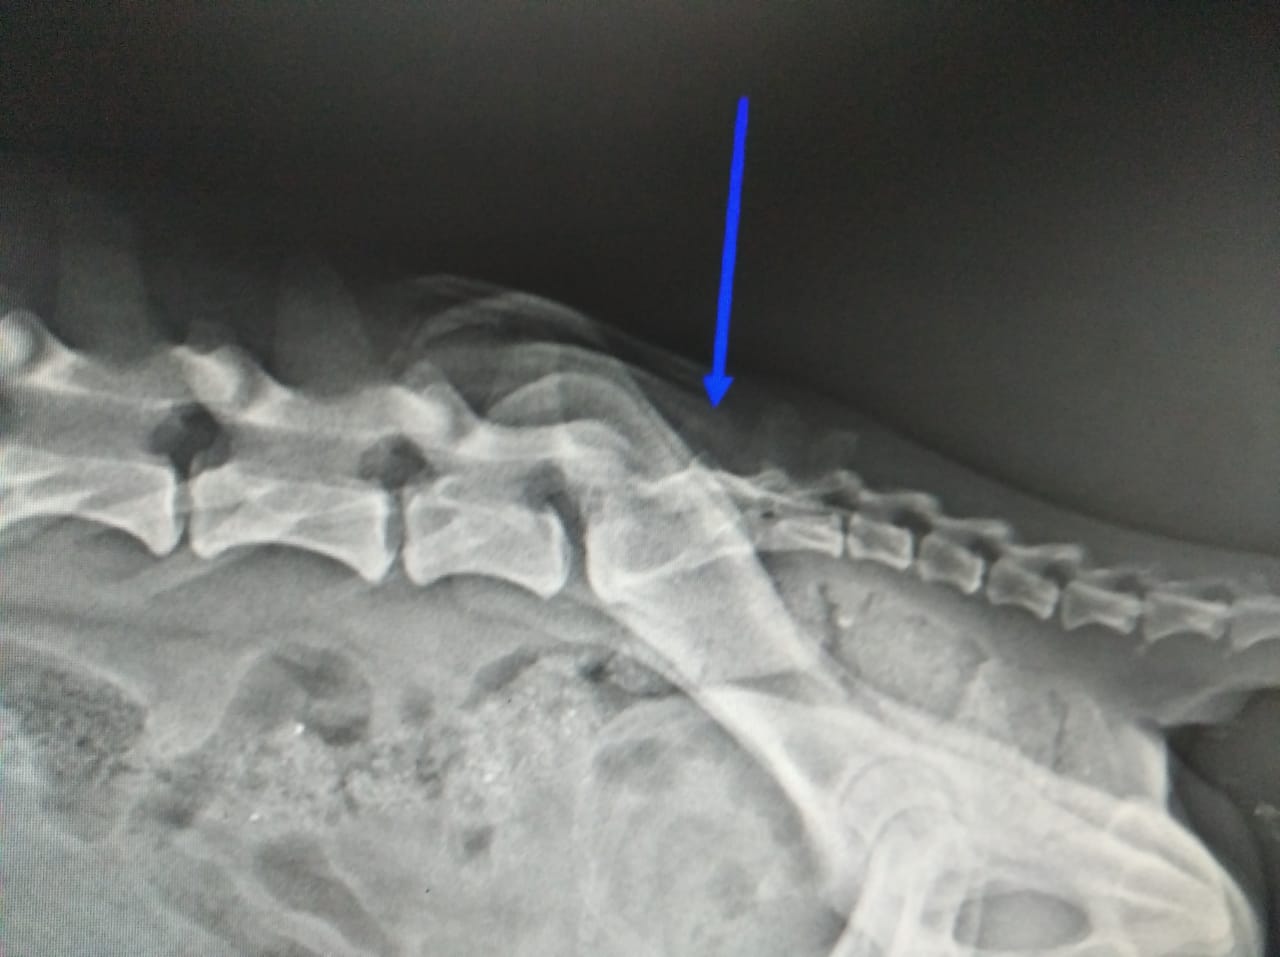

Apesar disso, a clínica deu hospedagem e medicamentos gratuitamente para o cachorro, que ainda está internado. Contudo, é necessário fazer um exame no valor de R$ 800 para verificar qual a real situação do animal e, ainda, uma cirurgia, que pode variar de R$ 1.800 a R$ 3 mil – se não for necessário colocar pino. Segundo informado pelos veterinários, é preciso realizar uma tomografia da coluna lombar, na região lombossacral – para verificar a suspeita de fratura na última vértebra lombar ou disjunção sacro ilíaca, quando pélvis desloca do lugar.

Os veterinários já sabem que precisam fazer a cirurgia. Porém, eles precisam fazer o exame para saber exatamente o problema do cão. De acordo com José Carlos, já foi feito um Raio-X, mas este só mostra o local danificado, não se houve rompimento dos ligamentos que auxiliam na mobilidade inferior do animal.